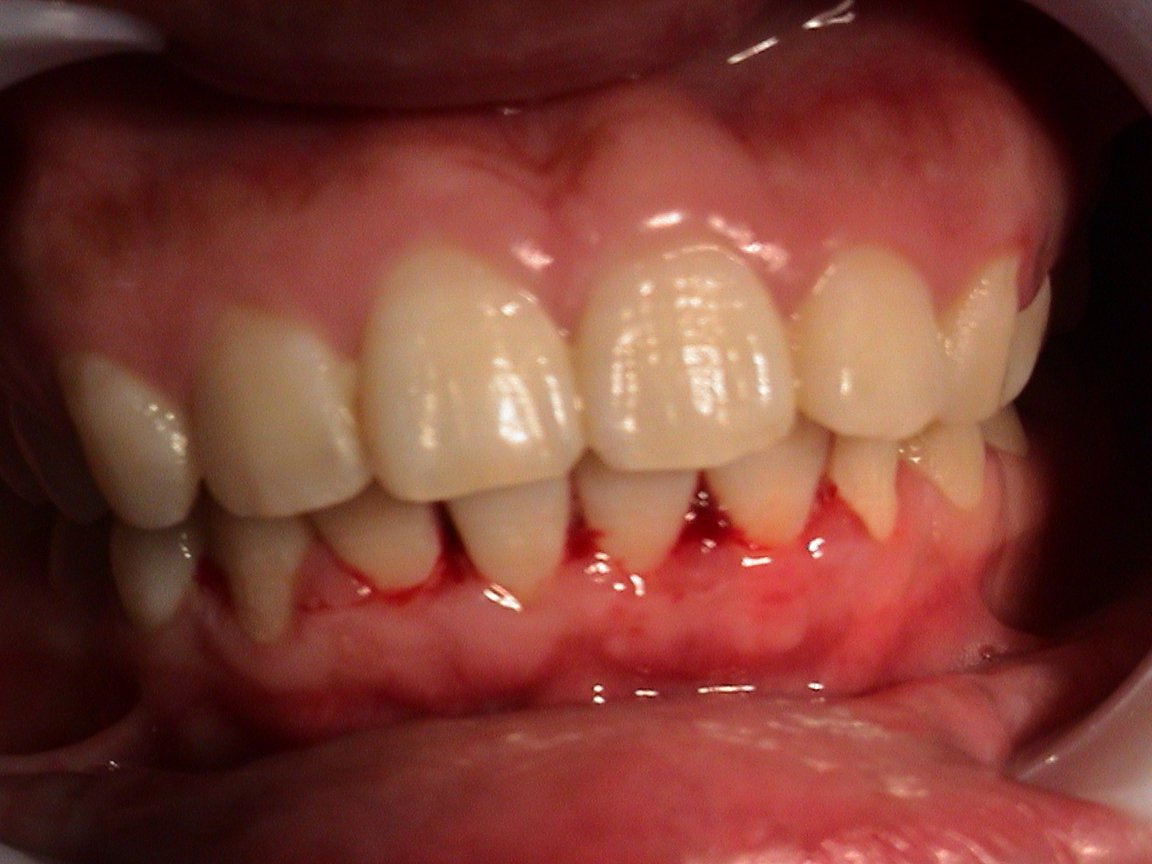

有些患者长期牙龈出血,每次刷牙的时候牙龈都会出血,刚开始可能没有意识到问题的严重性,但是时间久了牙龈出血的次数越来越频繁,严重影响到健康。那么长期牙龈出血怎么治呢?

牙龈出血大多数是由牙周病所引起的,可以通过药物治疗,如果口腔内有大量的牙菌斑和牙结石,就算通过其他方式治疗好了也只是暂时的,建议可以先洗牙,然后再治疗。